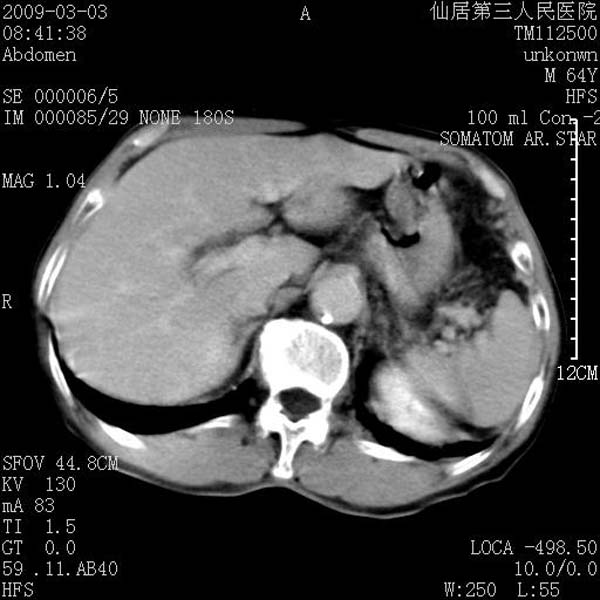

标题: CT18469:男性,64y,体检B超示肝脏低回声肿块,有胃溃疡手术 [打印本页]

标题: CT18469:男性,64y,体检B超示肝脏低回声肿块,有胃溃疡手术

患者,男性,64y,体检b超示肝脏低回声肿块,有胃溃疡手术史。

从平扫及增强的特点来看,支持肝脏腺瘤并出血。

ct值呢?感觉没强化,象囊性。

考虑肝静脉韧带裂区良性占位性病变(囊肿?)。

考虑肝囊肿并出血可能性大.

考虑高密度囊肿可能性大